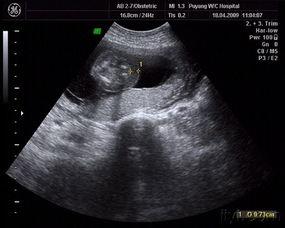

二、怀孕3个月胎儿图片赏析

接下来,让我们一起欣赏一些怀孕3个月胎儿图片,感受宝宝的成长变化。

1. 宝宝的脸部:从图片中可以看到,宝宝的脸部轮廓已经非常清晰,眼睛、鼻子、嘴巴等面部特征都开始显现。

2. 宝宝的四肢:宝宝的四肢开始变得更有力,手指和脚趾也开始分开,看起来就像一个小小的游泳运动员。

3. 宝宝的器官:通过图片可以看到,宝宝的器官正在逐渐发育,尤其是心脏,跳动得非常有力。

4. 宝宝的性别:有些图片中,宝宝的性别已经可以辨认出来,让人既期待又好奇。